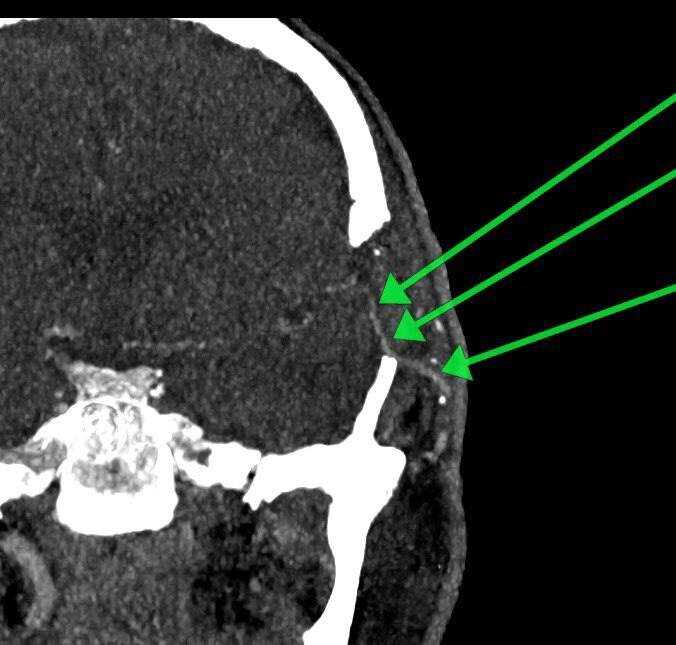

Нейрохирурги выполнили уникальную операцию 59-летнему пациенту, создав обходной путь для артерии, питающей мозг. Об этом сообщили в Минздраве Московской области.

«В течение почти четырех часов хирурги под микроскопом сшивали сосуды диаметром менее 2 миллиметров. Тем самым, мы успешно создали для кровотока новый путь», – рассказал нейрохирург Истринской больницы Николай Карпов.

На данный момент мужчину уже выписали, он находится дома на амбулаторном лечении. Контрольное обследование через месяц подтвердило: созданный «обходной путь» работает идеально, состояние пациента улучшается, а угроза повторного инсульта устранена